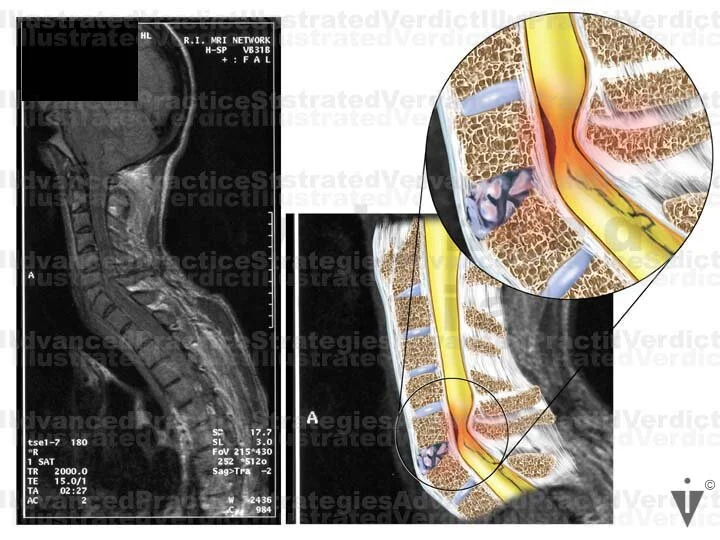

FILM ENHANCEMENT EXAMPLE 5

1. Film enhancement

2. Film

3. Film enhancement

4. Film